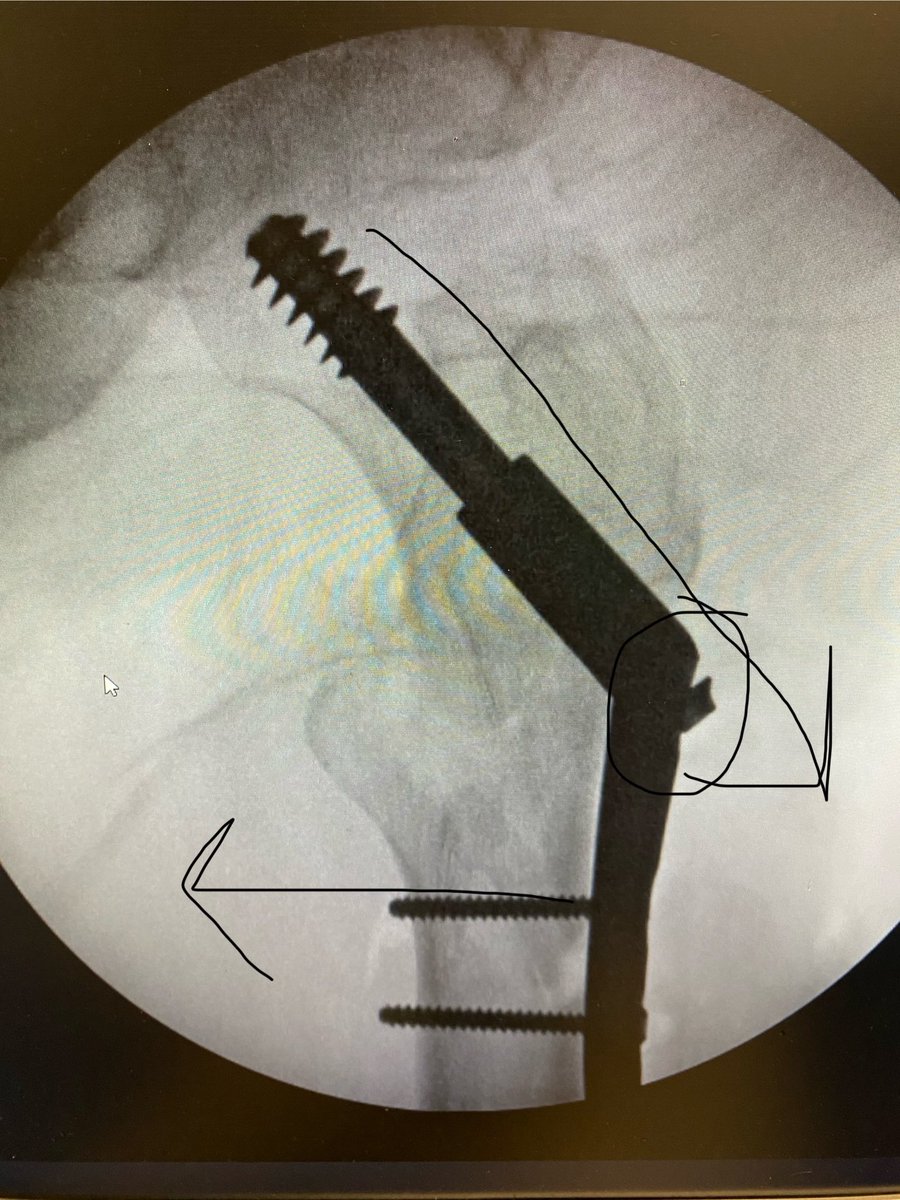

@sportsdoc2016 Even the interns know that this is a case to nail instead of DHS